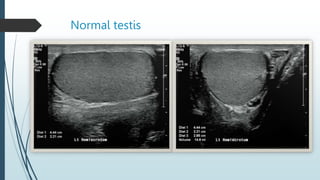

Normal testis.

Normal testis